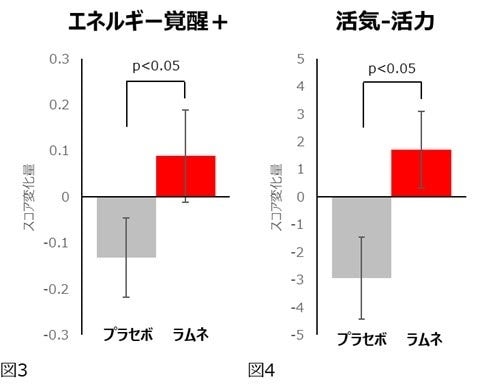

ラムネ摂取時はプラセボ摂取時と比較して、選択的注意力の指標であるフランカー課題の正答率が有意に上昇(図1)し、その時の脳血流(オキシヘモグロビン信号)が有意に増大(図2)しました。また、EACLの「エネルギー覚醒+」スコア(図3)とPOMS2短縮版の「活気‐活力」スコア(図4)が有意に上昇し、反対にネガティブ気分尺度である「怒り‐敵意」とTMDスコアが有意に低下しました。

この結果から、ラムネを摂取することによって認知テストにポジティブな気分で集中して取り組み、脳の一部の機能の活動が活性化することが示唆されました。本研究では集中して認知テストに取組んでいる時に脳の一部の活動が活性化していることを現象として捉えることができましたが、それらの関連性やメカニズムについては未解明な点も多く、今後の更なる研究が望まれます。